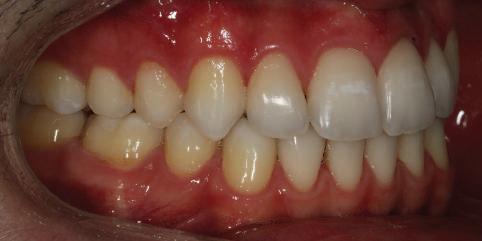

20 Dental Tribune Bulgarian Edition / октомври 2022 г. П ациентите със завършен растеж и скелетни проблеми обикновено представляват предизвикателство за ортодонт ската практика. Необходимостта от изваждане на зъби в комбинация с особеностите на възрастовата ортодонтия изисква особено внима ние. Фокусът върху критично важното значение на позицията на долните резци във връзка с дългосроч ната стабилност и постигането на оптимални оклузални взаимоотношения при затварянето на екстракционните пространства лесно може да излезе извън контрол. Когато към тези чисто кли нични проблеми се добави и стресът от натоваре ната практика, предизвикателството става още по-голямо. Всички тези фактори налагат използ ването на доказан подход с ясни и последовател ни стъпки, в което се разкрива силата на дисциплината „Алекзандър“ – предвидим протокол през целия процес на елиминиране на ротациите, ниве лиране на дъгите, затваряне на екстракционните пространства и финализиране на случая. Именно такъв е и случаят, който презентираме –екстракционен, скелетен клас 3 при възрастен па циент, лекуван по системата „Алекзандър“. ПРЕДВИДИМИ РЕЗУЛТАТИ ПРИ ПАЦИЕНТИ СЪС ЗАВЪРШЕН РАСТЕЖ И СКЕЛЕТЕН КЛАС 3, ИЗПОЛЗВАЙКИ ЕКСТРАКЦИОННО ЛЕЧЕНИЕ ПО ДИСЦИПЛИНАТА „АЛЕКЗАНДЪР“ Д-р Радой Димитров, България Преди започване на лечение клиничен случай | ортодонтия Фиг. 1а–1e Преди започване на лечение. Пациентът пристига в практиката с основното оплакване от невъзмож ност за нормално дъвчене. Снета е цялата необходима диагностична ин формация. Фиг. 1f–1h Снимки в профил и анфас. Фиг. 1i–1k Панорамна снимка, телерентгенография и анализ на телерент генография. Фиг. 1а Фиг. 1d Фиг. 1f Фиг. 1g Фиг. 1h Фиг. 1e Фиг. 1b Фиг. 1c Фиг. 1i Фиг. 1j Фиг. 1k

21Dental Tribune Bulgarian Edition / октомври 2022 г. ДИАГНОСТИЧНИ РЕЗУЛТАТИ: 1. Възраст на пациента: 21 години 2. Скелетен клас III (ANB 0) 3. Зъбен клас 3 4. Ръбцова захапка във фронта, кръстосана в дисталните участъци 5. Тясна горна челюст 6. Overjet – 0 мм, Overbite – 0 мм 7. Несъответствие на горната с долната средна линия 8. Единични контакти в ЦО 9. Хиподивергентен тип на растеж SN/MP – 33.5 10. Неравен гингивален контур 11. Неравна линия на усмивката 12. Тенденция за рецесии в долен фронт ПРЕПОРЪЧИТЕЛНО ЛЕЧЕНИЕ: Пълно ортодонтско лечение с метални брекети „Алекзандър“ Корекция на клас 3 захапката в областта на кучешките зъби с екстракция на първите пре молари в долна челюст Корекция на кръстосаната захапка в дистални участъци Коригиране на ръбцовата захапка във фронта Подобряване на ОJ и OB на пациента Стрипинг в долен фронт Подреждане на зъбите в горната и долната челюст Професионално хигиенизиране и профилактични дентални прегледи са препоръчителни на всеки 6 месеца. 1-ви месец След 1 месец са залепени брекети в горната челюст – поставена е еластична дъга. 016 NiTi. В долната челюст са елиминирани ротациите, поставена е стоманена дъга. 016SS, закалена с ток, и еластична верижка за затваряне на пространствата. 3-ти месец В долната челюст е поставена трета дъга – 17 x 25 NiTi с къси лигатури и верижка

В горната челюст се затварят пространствата с дъга .016SS и верижка. 5-и месец На 5-ия месец след залепяне на брекетите в долната челюст е поставена стоманена дъга 16 x 22 SS с четвъртито сечение, омега луп и тай бек. В горната челюст е поставена дъга 17 x 25 NiTi. Поради липсата на стабилни оклузални контакти са поставени лингвални верижки в областта на моларите, за да се предотврати нежелана ротация на 7-ите зъби. 6-и месец На 6-ия месец от началото на лечението са екстрахирани долните първи премолари, поставена е дъга 16 x 22 SS със затваряща чупка teardrop. Чупката се активира всеки месец по 1 мм с чинч-бек. клиничен случай | ортодонтия СТЪПКИ НА ЛЕЧЕНИЕТО Начало на лечението Лечението започва с поставяне на апарат за бърза експанзия в горната челюст. През първия месец от лечението са направени 24 оборота на апарата за експанзия. Залепени са брекети в долната челюст, поставена е дъга 17x25 CuNiTi, като са предпи сани клас 3 ластици (1/4”,4 1/2 oz) по време на сън, за да се осигури контрол върху торка на долните резци. Фиг. 2а Фиг. 3a Фиг. 4a Фиг. 3b Фиг. 4b Фиг. 3c Фиг. 4c Фиг. 3d Фиг. 4d Фиг. 3e Фиг. 4e Фиг. 5a Фиг. 5b Фиг. 5c Фиг. 5d Фиг. 5e Фиг. 6a Фиг. 6b Фиг. 6c Фиг. 6d Фиг. 6e Фиг. 7a Фиг. 7b Фиг. 7c Фиг. 7d Фиг. 7e Фиг. 2b Фиг. 2c Фиг. 2d

Dental Tribune Bulgarian Edition / октомври 2022 г.22 клиничен случай | ортодонтия 14-и месец В горната и долната челюст са поставени последни стоманени дъга с омега луп и тай бек – 17 x 25 SS с четвъртито сечение. Назначени е ластик за средната линия в комбинация с клас 3 ластик (1/4”, 6 1/2 oz). Контролни рентгенографии 13-и месец Екстракционните пространства са затворени. Направена е контролна панорамна снимка за оценка позицията на корените. Взето е решение за презалепване на брекетите на 12, 22 и пръстените на 36 и 46. 21-ви месец Средната линия в горната и долната челюст съвпадат. Ластиците са спрени. Свалени са пръстените и брекетите в горната и долната челюст, зигзаг ластици не са използвани поради благоприятните оклузални взаимоотношения. Фиг. 11j Ортопантомография в края на лечението. Фиг. 11k Телерентгенография след края на лечението. Фиг. 11l Анализ на телерентгенографията след лечението. Фиг. 11m Последователност на дъгите в горната и долната челюст Фиг. 11n Суперимпозиция на PreOp и PostOp ортопантомографии. 10-и месец Затварянето на пространствата е предвидимо и контролирано, без да се отварят пространства в зъбната дъга. Фиг. 8a Фиг. 8b Фиг. 8c Фиг. 8d Фиг. 8e Фиг. 10a Фиг. 10b Фиг. 10c Фиг. 10d Фиг. 10e Фиг. 9a Фиг. 9b Фиг. 9c Фиг. 9d Фиг. 9e Фиг. 9f Фиг. 11a Фиг. 11f Фиг. 11j Фиг. 11l Фиг. 11m Фиг. 11n Фиг. 11k Фиг. 11g Фиг. 11h Фиг. 11i Фиг. 11b Фиг. 11c Фиг. 11d Фиг. 11e

Dental Tribune Bulgarian Edition / октомври 2022 г. 23клиничен случай | ортодонтия реклама Лечението е продължило 21 месеца. Проведено е домашно избелване с индивидуални шини. За автора: Д-р Радой Димитров завършва с отличие Факултета по дентална медицина към МУ–София през 2015 г. В продължение на 5 години работи в няколко водещи практики в София, като през 2019 г. заедно със своята съпру га д-р Траяна Димитрова основават собствена практика в гр. Гоце Делчев –Dimitrovi Dental Care. Посещава редица курсове за повишаване на квалификаци ята, но най-сериозен тласък в развитието на ортодонтската си практика получава след завършването на комплексната ортодонтска програма, воде на от д-р Иван Горялов, базирана на дисциплината „Алекзандър“ – система с повече от 50 години опит в целия свят. Д-р Димитров е член на Българския изследователски клуб „Алекзандър“. Взе ма участие като гост-лектор в симпозиума с международно участие The Power of the Alexander Discipline, който се проведе на 14–15.05.2022 г. С д-р Ди митров можете да свържете на тел. +359885 252 025. Заключение Представеният случай е ярък пример за възможностите и красо тата на дисциплината „Алекзандър“ – приложен е утвърден под ход с ясни правила и са постигнати очакваните цели. Резулта тът ще бъде дългосрочно стабилен, тъй като са спазени всички правила, които се отнасят към максимално комфортната пози ция на зъбите в края на лечението. Постигнати са красива усмив ка и стабилна оклузия. ПОСТИГНАТИ РЕЗУЛТАТИ ОТ ЛЕЧЕНИЕТО 1. Коригирана ръбцова захапка 2. Коригирана клас 3 захапка в областта на ку чешките зъби 3. Коригирана кръстосана захапка в дисталните участъци 4. Коригиран овърджет и овърбайт 5. Разширена е горната зъбна дъга 6. Подредени зъби в горната и долната челюст 7. Постигната е стабилна захапка с множество контакти в ЦО 8. Драматично е подобрена дъвкателната функ ция 9. Подобрена е линията на усмивката ДРУГИ ПРОВЕДЕНИ ДЕНТАЛНИ ПРОЦЕДУРИ 1. Домашно избелване на зъбите 2. Екстракция на мъдреците Фиг. 12a Фиг. 12b Фиг. 12c Фиг. 12eФиг. 12d Фиг. 12f Фиг. 12g Информация за дати, цени и отстъпки www.bracescourses.com 0889 22 55 01 Практически курсове лектор д-р Иван Горялов Дисциплината „Алекзандър“ ПЪТЯТ КЪМ СУПЕРУСМИВКИТЕ 100% връщане на цялата сума, ако не сте удовлетворени след преминаване на Ниво 1 Директно и индиректно залепяне на брекети Анализ, диагноза и план на лечение Лечение на клас 2 дълбока захапка Екстракционно лечение Лечение на клас 3 отворена захапка НИВО 5НИВО 1 НИВО 2 НИВО 3 НИВО 4